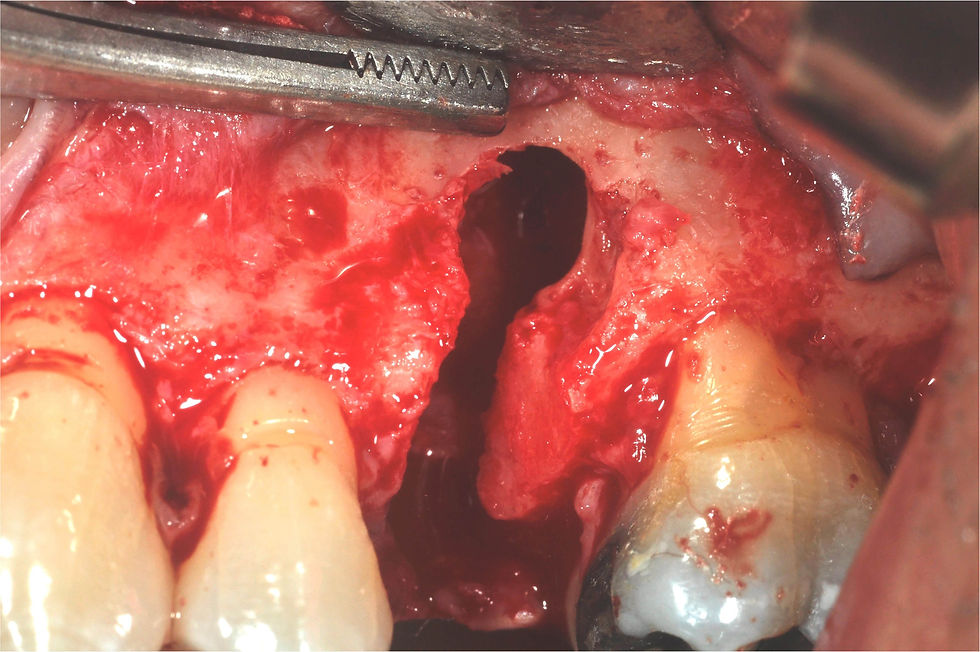

Preparation of the surgical site.